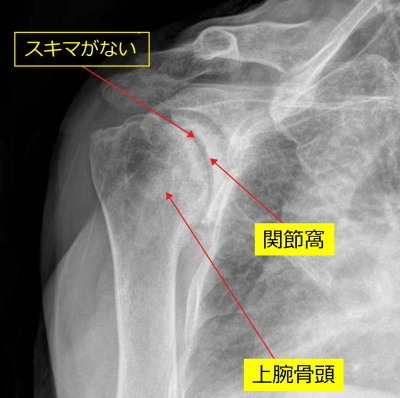

【正常、人工関節置換術の術前、術後のレントゲン】

正常

上腕骨頭に丸みがあり、関節窩と上腕骨頭にすきまがあります。

手術前のレントゲン

上腕骨の変形が強い所見がみられます。上腕骨頭の丸みがなくなっています。